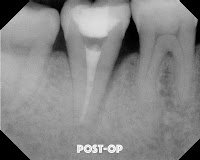

Unfortunately, at the 2 year re-evaluation, the lateral lesion did not resolve. Since I’m working on a periodontist friend of mine, why not try a retreat again? We tried it and again found no root fracture, or obvious reason for the failure to heal.